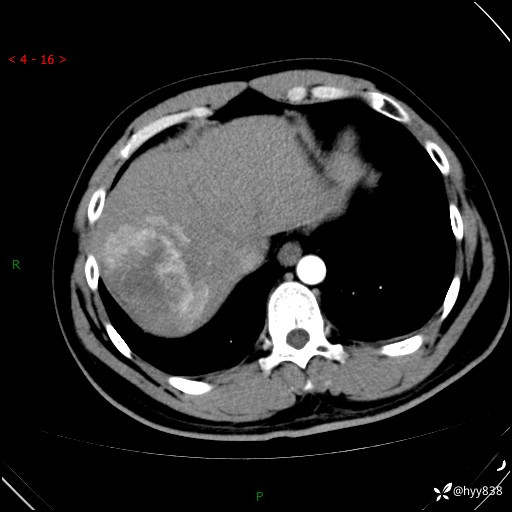

增强动脉期

静脉期